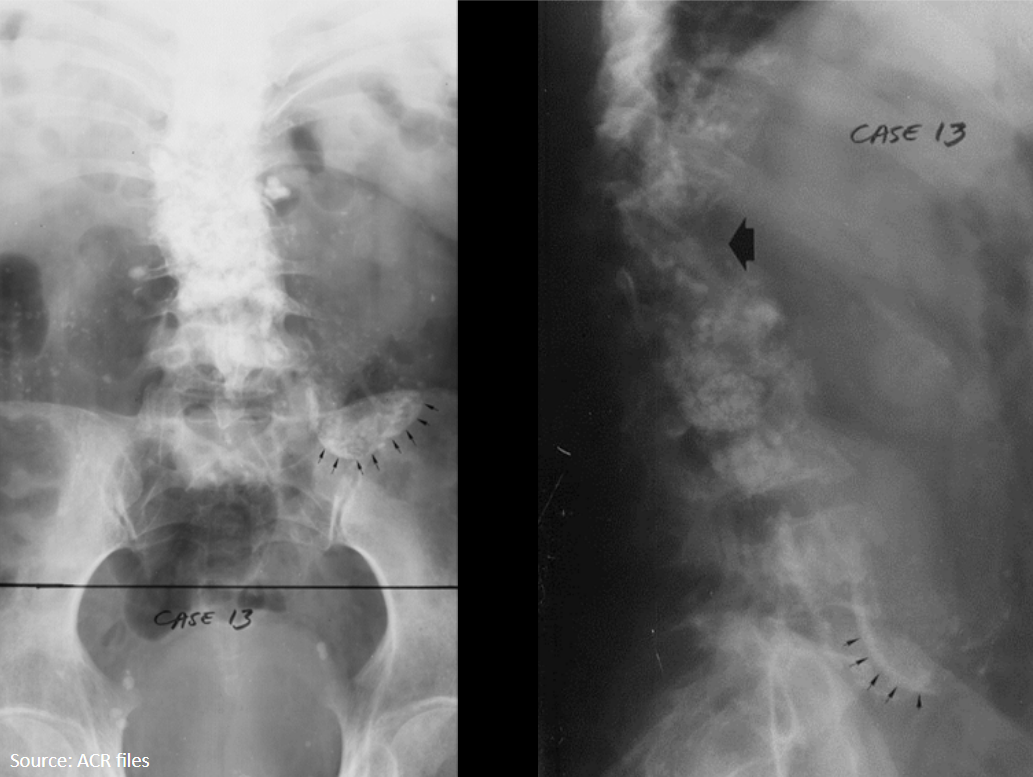

13

Q

10-year-old female presents with a painful limp.

What is the diagnosis?

A

LCP

Legg-Calve-Perthes

sclerosis and flattening with epiphyseal fragmentation of femur (AVN)